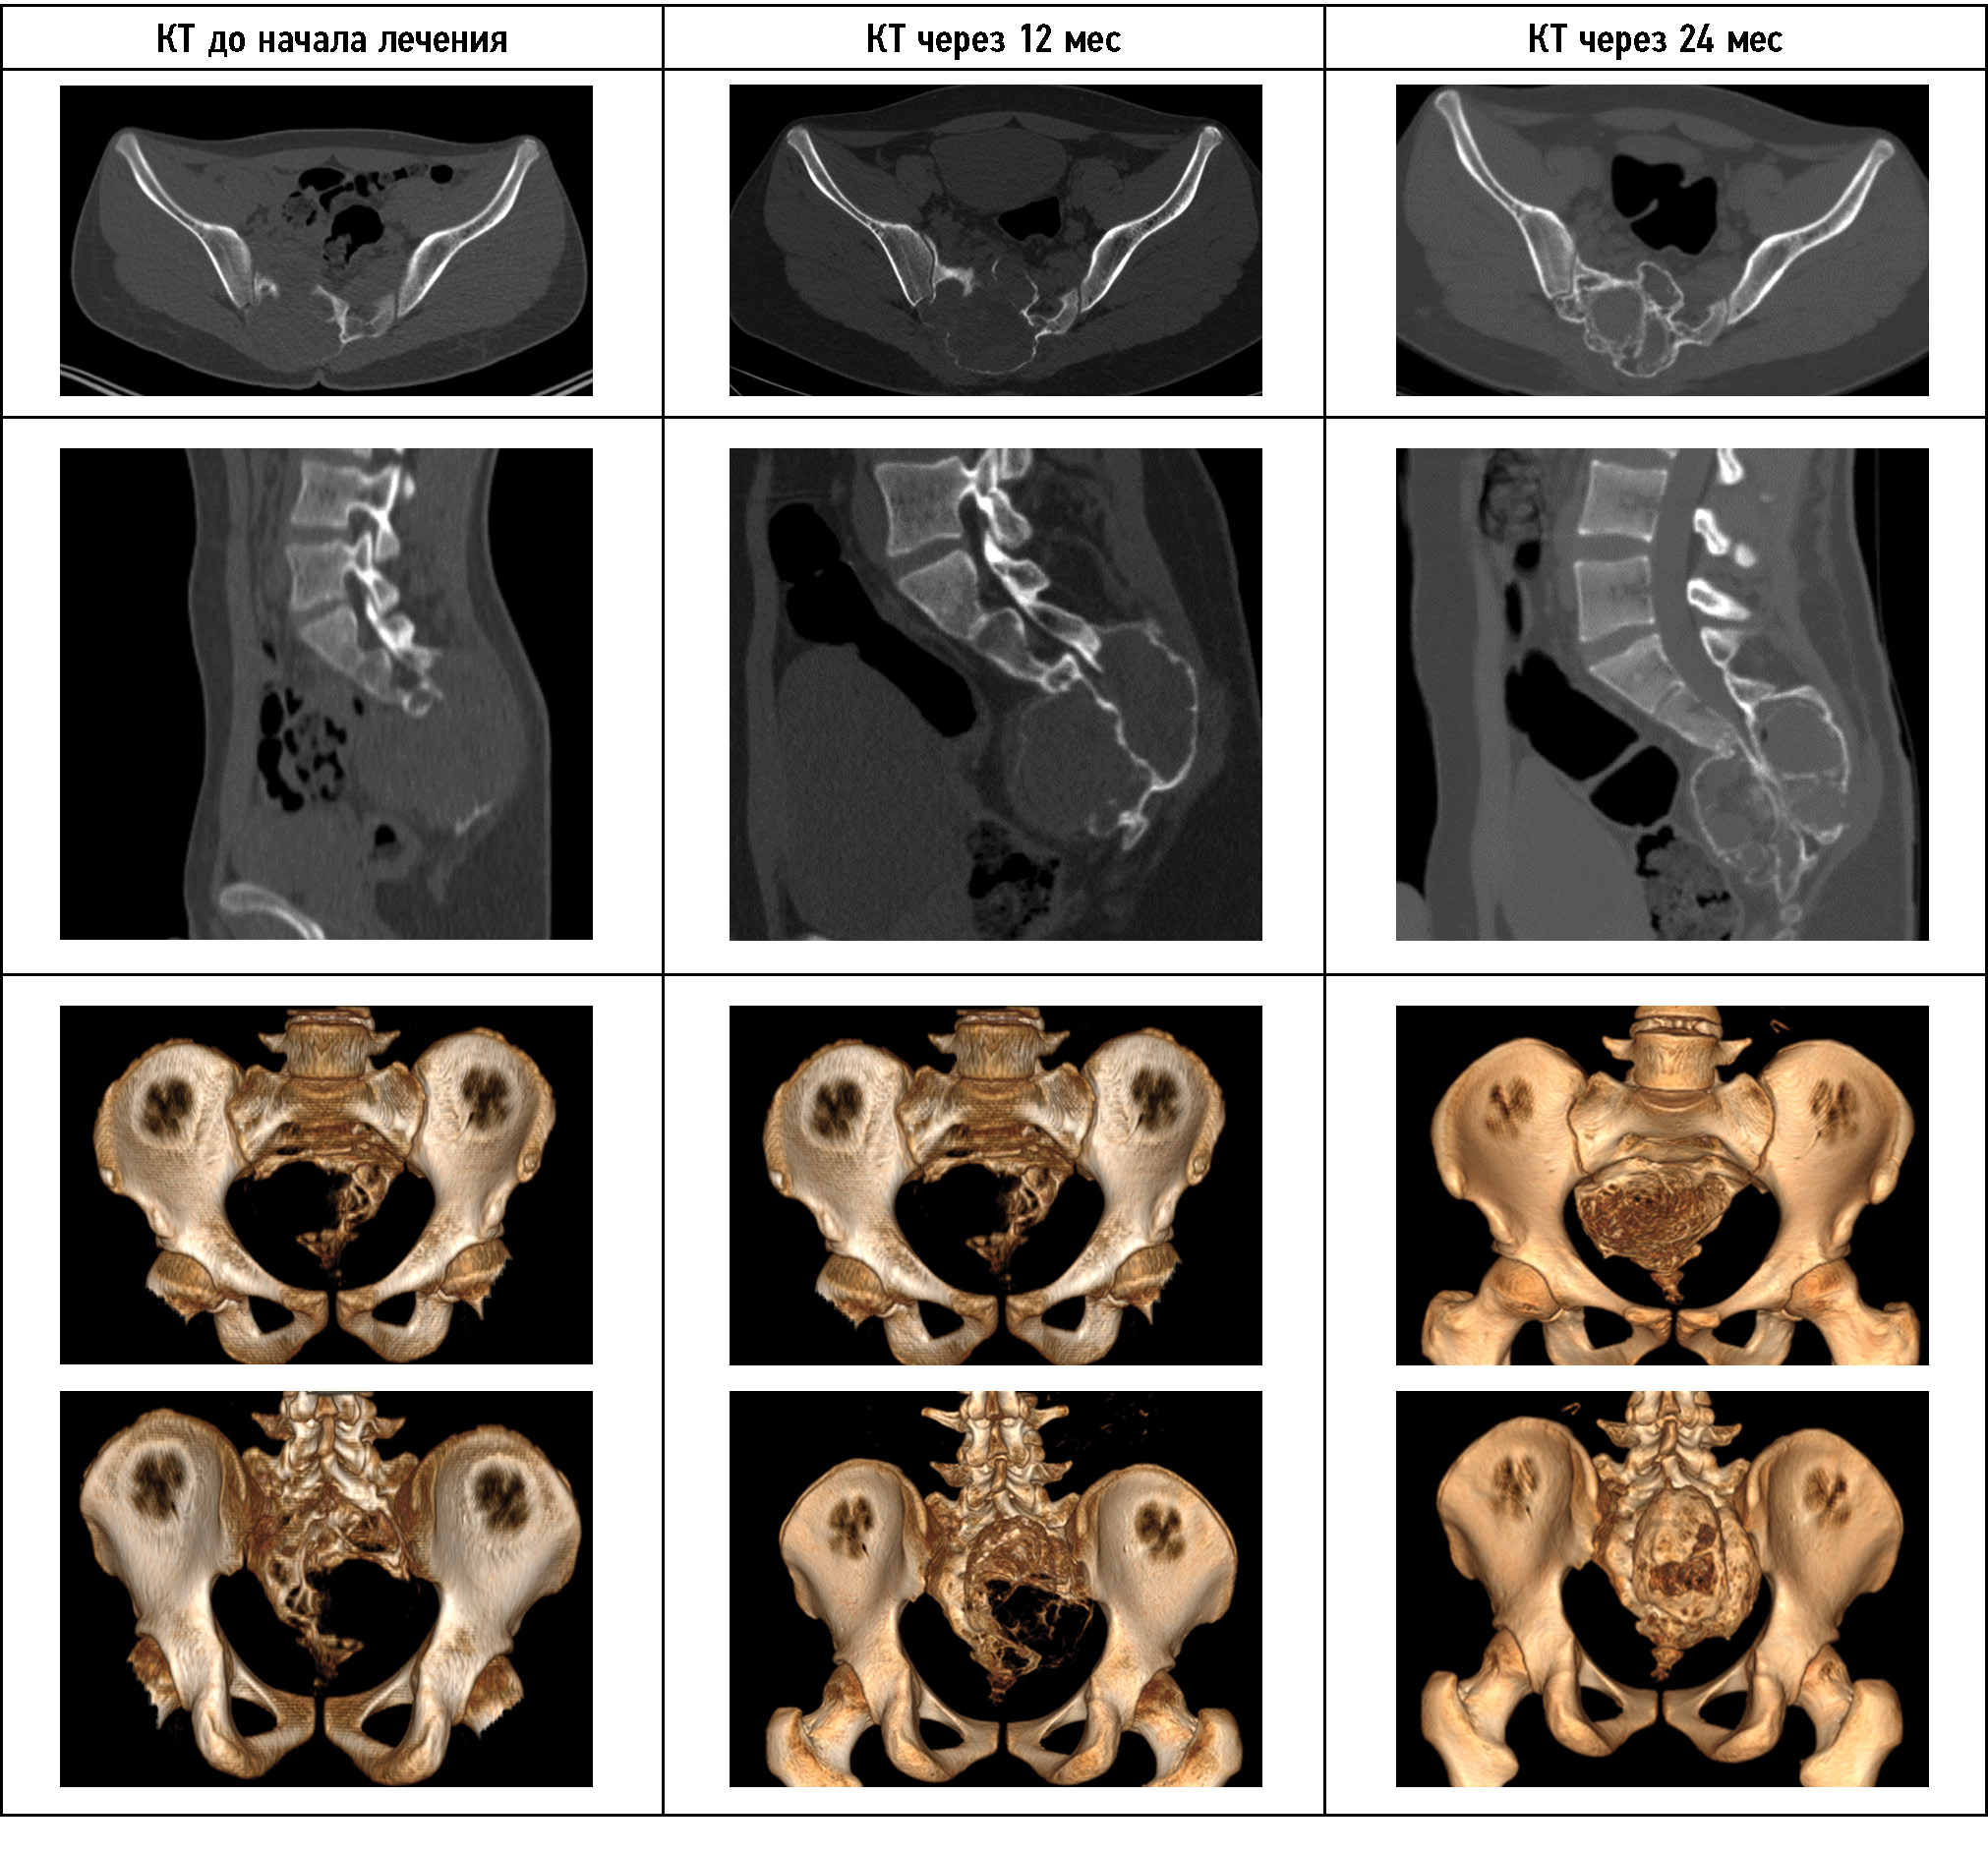

Рис. 5. КТ-динамика лечения пациента 2. Отчётливо прослеживается формирование костной ткани внутри кисты.

Fig. 5. The CT-dynamics of the patient’s treatment show that bone tissue is forming inside the cyst.

На момент первой госпитализации возраст пациента составлял 14 лет. Госпитализирован в медицинское учреждение по месту жительства с сильными болями в крестцовой области. В июле 2021 г. по месту жительства выполнена открытая биопсия патологического очага, диагноз «аневризмальная костная киста» подтверждён гистологически. При первом поступлении в отделение предъявлял жалобы на боль в области крестца до 9–10 баллов по ВАШ, боль иррадиировала в правую ногу до пятки. Срок жалоб составил 9 месяцев, попытки консервативного лечения (физиотерапевтическое лечение, лечебная физкультура, нестероидные противовоспалительные препараты) по месту жительства — без положительной динамики. При поступлении отмечена выраженная сгибательная контрактура правого тазобедренного и коленного сустава, пациент находится в вынужденном положении, самостоятельно не передвигается, не сидит из-за болевого синдрома. Пункционное лечение начато в августе 2021 г. Исследования выполнены в медицинском учреждении по месту жительства (рис. 4), далее проведена открытая биопсия патологического очага. Определяются уровни жидкости и стеноза невральных структур по данным МРТ, поражение S2-S5 позвонков с частичной аплазией копчика, смещение органов малого таза опухолью. На КТ-исследовании, выполненном в период первой госпитализации, определяется продолженный рост опухоли после выполнения открытой биопсии. Разница между исследованиями составляет один месяц. В этом случае можно говорить о высокой агрессивности патологического процесса. Первый этап пункционного лечения начат в августе 2021 г. При оценке внутрикистного давления во время первой пункции был получен показатель 720 мм вод. ст. КТ-картина через 3 месяца продемонстрировала признаки частичной репарации, нарастание костных перегородок, частичное окостенение оболочек опухоли. При повторных пункциях отмечалось снижение внутрикистного давления. На момент этапной операции спустя 5 месяцев от начала лечения внутрикистное давление составило 389 мм вод. ст. Также отмечается увеличение объёма движений в коленном и тазобедренном суставе правой ноги. У пациента появилась возможность сидеть и передвигаться при помощи ходунков. Спустя 10 месяцев с начала лечения (20 пункций) по данным КТ определяются выраженные признаки репарации аневризмальной костной кисты, образование костных трабекул, снижение объёма опухоли, снижение компрессии органов таза (рис. 5). Пациент ходит самостоятельно, боль во время ходьбы не определяется, сидит свободно. Походка нарушена в связи со слабостью мышц нижних конечностей. При пункции снижение внутрикистного давления до 124 мм вод. ст. Пациент продолжает пункционное лечение.